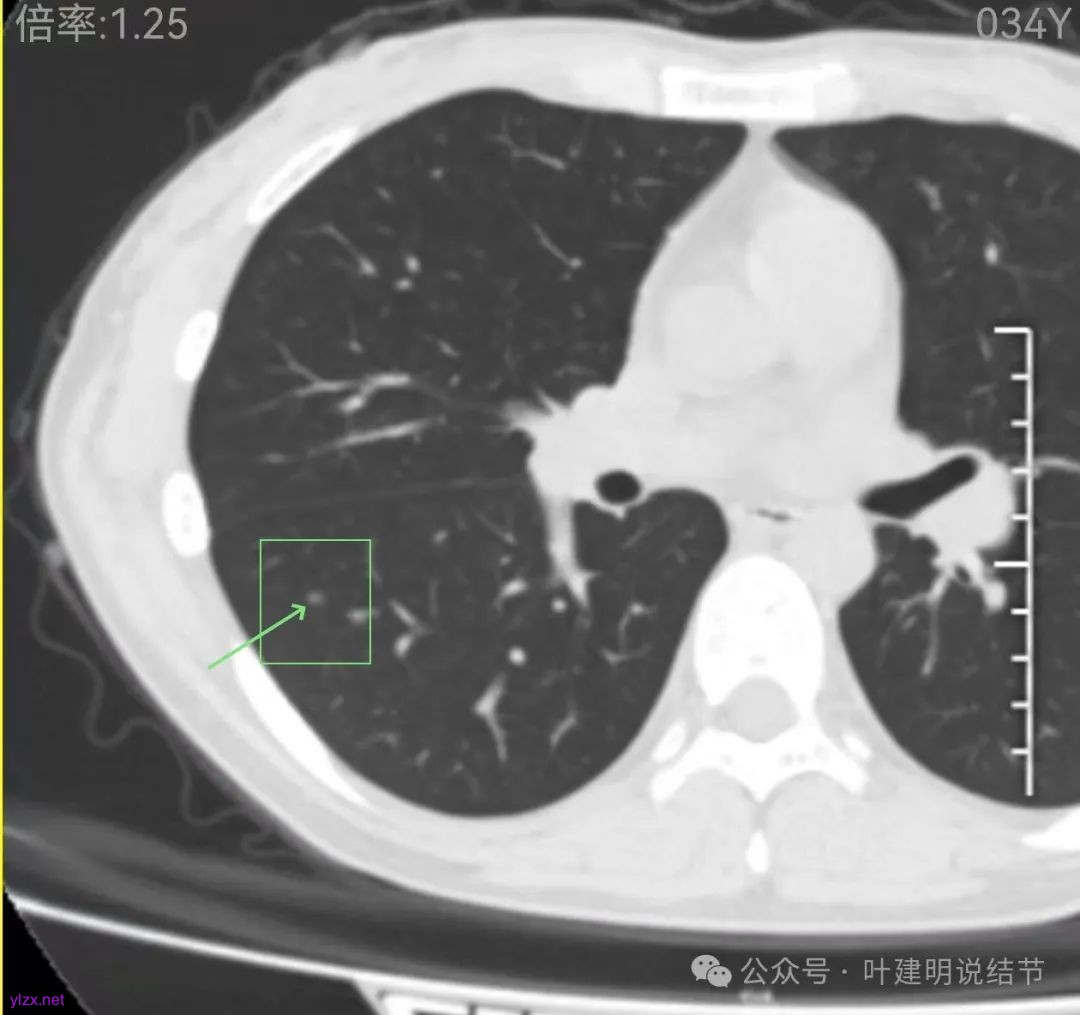

再看中间2023年的影像:

右下此灶2023年时此层面淡而边显糊。

上图层面已经像混合密度了,表面毛糙不光滑,灶内密度不均,也有小空泡征的样子。

感觉这处(在上截图结节的下面点,邻近层面)不像前面病灶的延伸,否则这密度的变化有点突兀呀。

两肺多发结节,左侧黄色标注的考虑是肺泡上皮增生可能性大;蓝色的考虑肺泡上皮增生或者少许慢性炎可能性大;右侧红色宽起来并带有红色箭头的这处是主病灶,偏混合密度,整体轮廓较为清楚,边缘显得毛糙,从2024年12月份的来看,要考虑是肿瘤范畴,原位癌或者微浸润性腺癌可能性较大,也不能完全排除不典型增生。但是在2022年的时候,这个病灶的边上也有一个实性的微小结节,如果只看2022年的,这么小的实性结节,又比较圆,表面也显得较为光滑,是要考虑良性的,当然太小了需要动态观察。回头再重新来看2024年底的,发现绿色箭头所指的这个微小实性的较2022年几乎没有变,去仔细寻找2022年的,发现当时在实性结节旁边也有密度很淡的一点磨玻璃影(也可能真的就是一处,只是扫描不够薄,密度的变化有些突兀而已),而到了2024年12月份,实性微小这处没有明显变化,但是原来很淡的磨玻璃变成了混合磨玻璃,范围也明显扩大。所以总体来看右肺下叶这处是考虑恶性的,而且从磨玻璃结节角度来讲,还是生长比较快的,就是说还是有一定风险的。加上左侧还有两处也是磨玻璃持续存在,虽然边缘轮廓显模糊一点,但多年以后也可能仍然要变成原位癌或者微浸润性腺癌之类的东西。通盘考虑以后,我倾向于右侧近期单孔胸腔镜下微创局部切除,左侧随访观察,等到有进展并风险增加再来考虑处理。意见供参考!